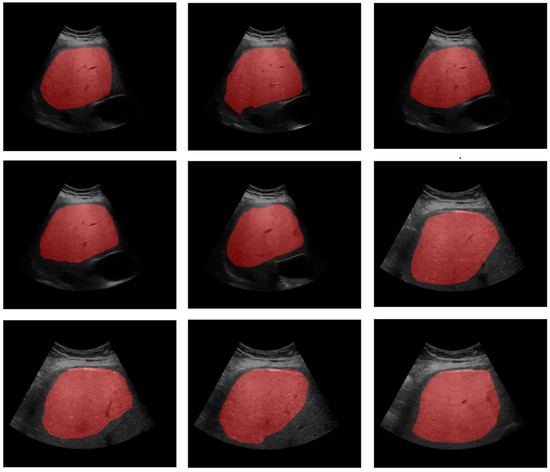

Adaptive Evolutionary Optimization of Deep Learning Architectures for Focused Liver Ultrasound Image Segmentation

2. Materials and Methods